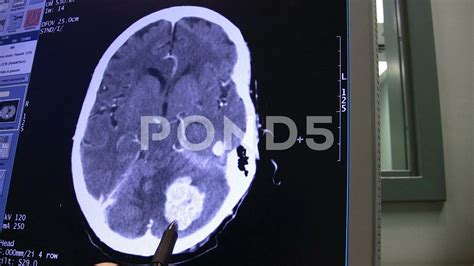

A brain cancer CT scan, or Computed Tomography scan, is a sophisticated diagnostic imaging test that uses X-ray technology to capture detailed cross-sectional images of the brain. Unlike a standard X-ray, which produces a single flat image, a CT scan takes multiple images from various angles and uses computer processing to create comprehensive "slices" of the internal structures of the head. This allows radiologists to examine the brain tissue, blood vessels, and bone structures in high definition.

Doctors often order this scan if they suspect an abnormality such as a tumor, cyst, or inflammation. By visualizing the physical landscape of the brain, medical experts can identify the location, size, and shape of potential growths, which is crucial for determining the next steps in a clinical treatment plan.

Interpreting the Results

Once the scan is complete, a radiologist—a doctor specialized in interpreting medical images—will analyze the data. They look for masses, swelling, or structural anomalies that could indicate cancer or other conditions. The results are typically sent to your primary physician or neurologist, who will then discuss the findings with you during a follow-up appointment.

It is important to remember that a "positive" finding on a scan does not automatically confirm cancer. Many non-cancerous conditions, such as benign cysts or infections, can mimic the appearance of a tumor. Further diagnostic procedures, such as a biopsy or an MRI with gadolinium contrast, may be required to reach a definitive diagnosis.